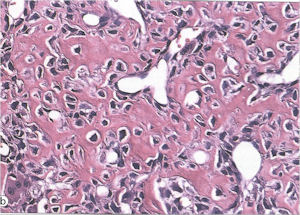

Aggressive Osteoblastoma

- Aggressive osteoblastoma is a distinct rare type of osteoblastoma that has a much more aggressive local behavior than a conventional osteoblastoma. They have a higher chance for local recurrence after removal.

- There has been controversy about the true existence of this type of tumor and whether these tumors are actually low grade osteosarcomas.

- They have a similar appearance microscopically as a conventional osteoblastoma except the osteoblasts are twice as large and have an epithelioid quality with abundant eosinophilic cytoplasm (Epithelioid Osteoblasts).

- Aggressive osteoblastoma is a borderline lesion lesion between osteoblastoma and osteosarcoma. It is not a precursor to osteosarcoma. It does not metastasize.